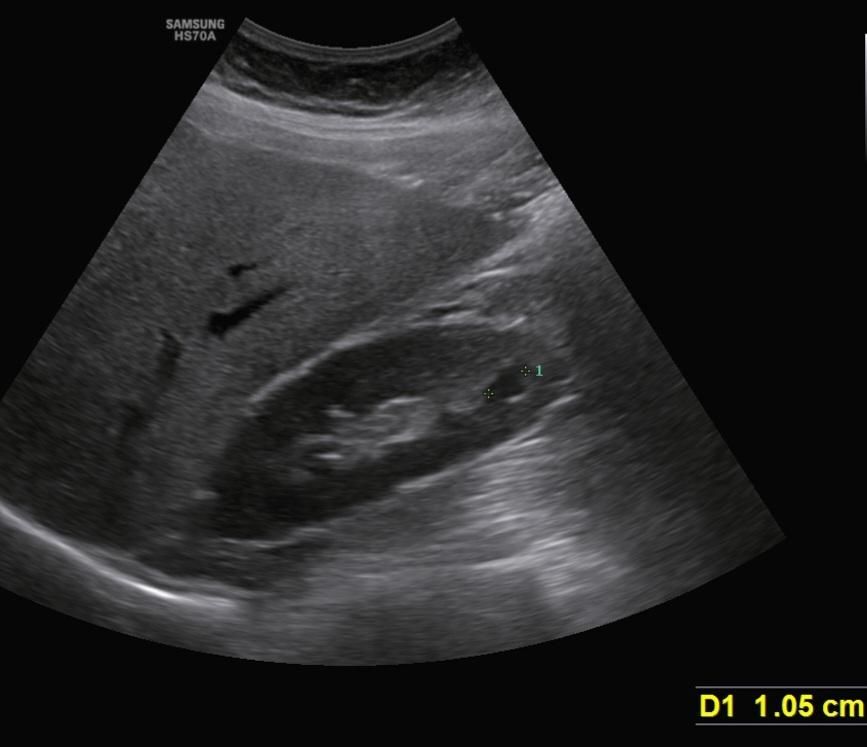

그리고 이번년도에 복부초음파에서 1.05cm 발견했어요.

9.75mm에서 1.05cm면 자라난건가요...?

복부초음파 사진을 올립니다.

• 4번 째 사진

초음파의 경우 정해진 plane이 없기 때문에 1:1 matching으로 비교하는 것은 무리가 있습니다.

단지 검사자가 해당병변의 최대(maximal) 직경(diameter)을 측정하였다고 가정하고 20% 이상 증가를 했다면

크기가 컸다고 고려합니다. 환자분의 경우 9.75mm 에서 10.5mm로 증가하였으니 계산해보면 7%가량 증가한 것 같은데 이런 경우에는 증가했다고 보기는 어렵습니다. 그걸 떠나서 낭종의 크기가 너무 작아요 1cm 근처인 완전낭종은

아무도 문제삼거나 하지 않습니다. 이 정도 크기면 작아서 어떤 검사에서는 보이지 않을 수도 있을 것 같습니다.